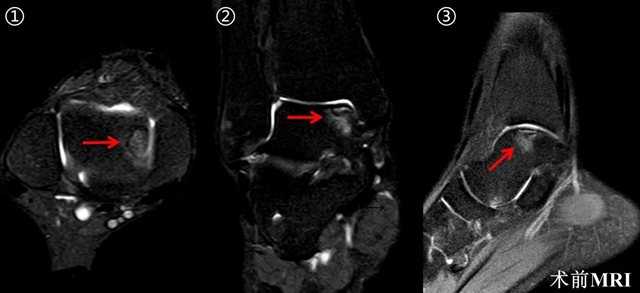

经仔细查体并完善相关检查后,诊断其为“右踝关节距骨骨软骨损伤”,鉴于病情反复,软骨损伤面积较大,建议住院手术治疗。

在科室副主任关钛元教授组织专家经过认真讨论后,认为其软骨损伤面积超过120m㎡,损伤深度超过12mm,并且伴软骨下骨囊肿形成,分型为Hepple V型,保守治疗及微骨折术治疗疗效有限,后期可能发展为创伤性踝关节炎,张磊教授建议行“踝关节镜检清理+新型半斜型内踝截骨+取同侧膝关节软骨行马赛克软骨移植术。”